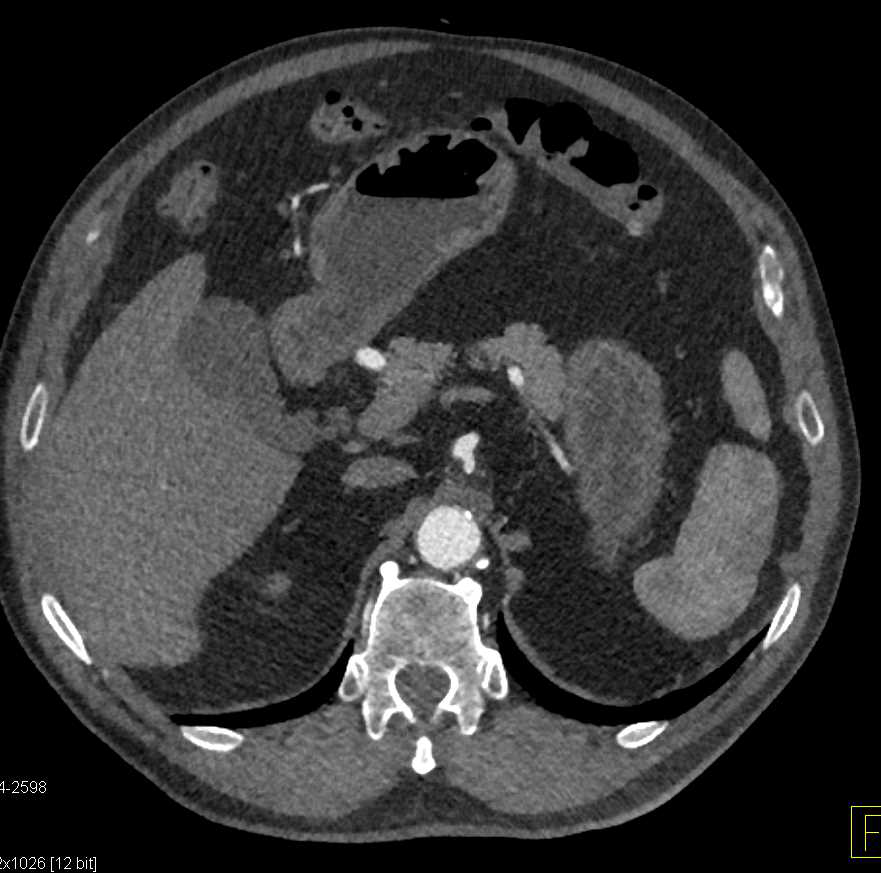

CCTA with Aneurysm of the Left Main Coronary Artery